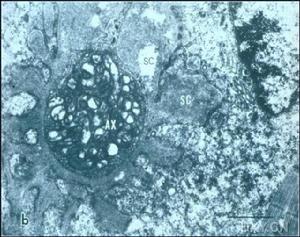

(3)電鏡檢查:有少數文獻報導藥物性ATIN電鏡表現。Ooi等發現小管細胞線粒體腫脹,粗面內質網顯著擴張,遠端小管病變較近端小管嚴重。皮質小管的管周基底膜增厚並分成多層,增厚的原因可能是基底膜物質的增生。由於間質結構的破壞,間質區域的病變被Galpin等描述為混亂病變(chaotic)。炎性浸潤的細胞由淋巴細胞、漿細胞和嗜酸細胞組成,有少量中性粒細胞。腎小球一般正常,只在並發腎病綜合徵的藥物性ATIN病例發現明顯的足突融合。